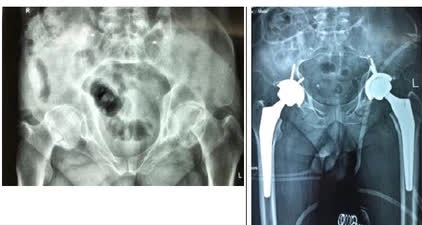

Ảnh phim chụp người bệnh trước và sau phẫu thuật

Người bệnh đã được các bác sĩ tiến hành thay cùng lúc cả hai bên khớp háng. Các bác sĩ nhận định, nếu thay từng bên một, người bệnh sẽ phải chờ thêm 1-2 tuần khi một bên sau phẫu thuật đã ổn định. Như vậy thời gian chăm sóc sẽ kéo dài, người bệnh vẫn đau đớn và phải chống chọi với những biến chứng do nằm lâu nên quyết định thay cả hai khớp háng cùng lúc. Việc thay khớp háng cùng lúc đòi hỏi mổ rất nhanh, gây mê hồi sức bảo đảm, trang thiết bị đầy đủ, theo dõi và hồi sức sau phẫu thuật chu đáo và cẩn thận mới an toàn cho người bệnh.Sau phẫu thuật người bệnh tiếp tục được theo dõi và điều trị tại Khoa Phẫu thuật Chi trên và Y học thể thao, Bệnh viện Hữu nghị Việt Đức. PGS.TS Nguyễn Mạnh Khánh cho biết, dự kiến sau một ngày phẫu thuật bệnh nhân có thể ngồi dậy được, sau hai ngày phẫu thuật người có thể tập đi sớm với sự hỗ trợ của nạng/khung trợ đỡ.